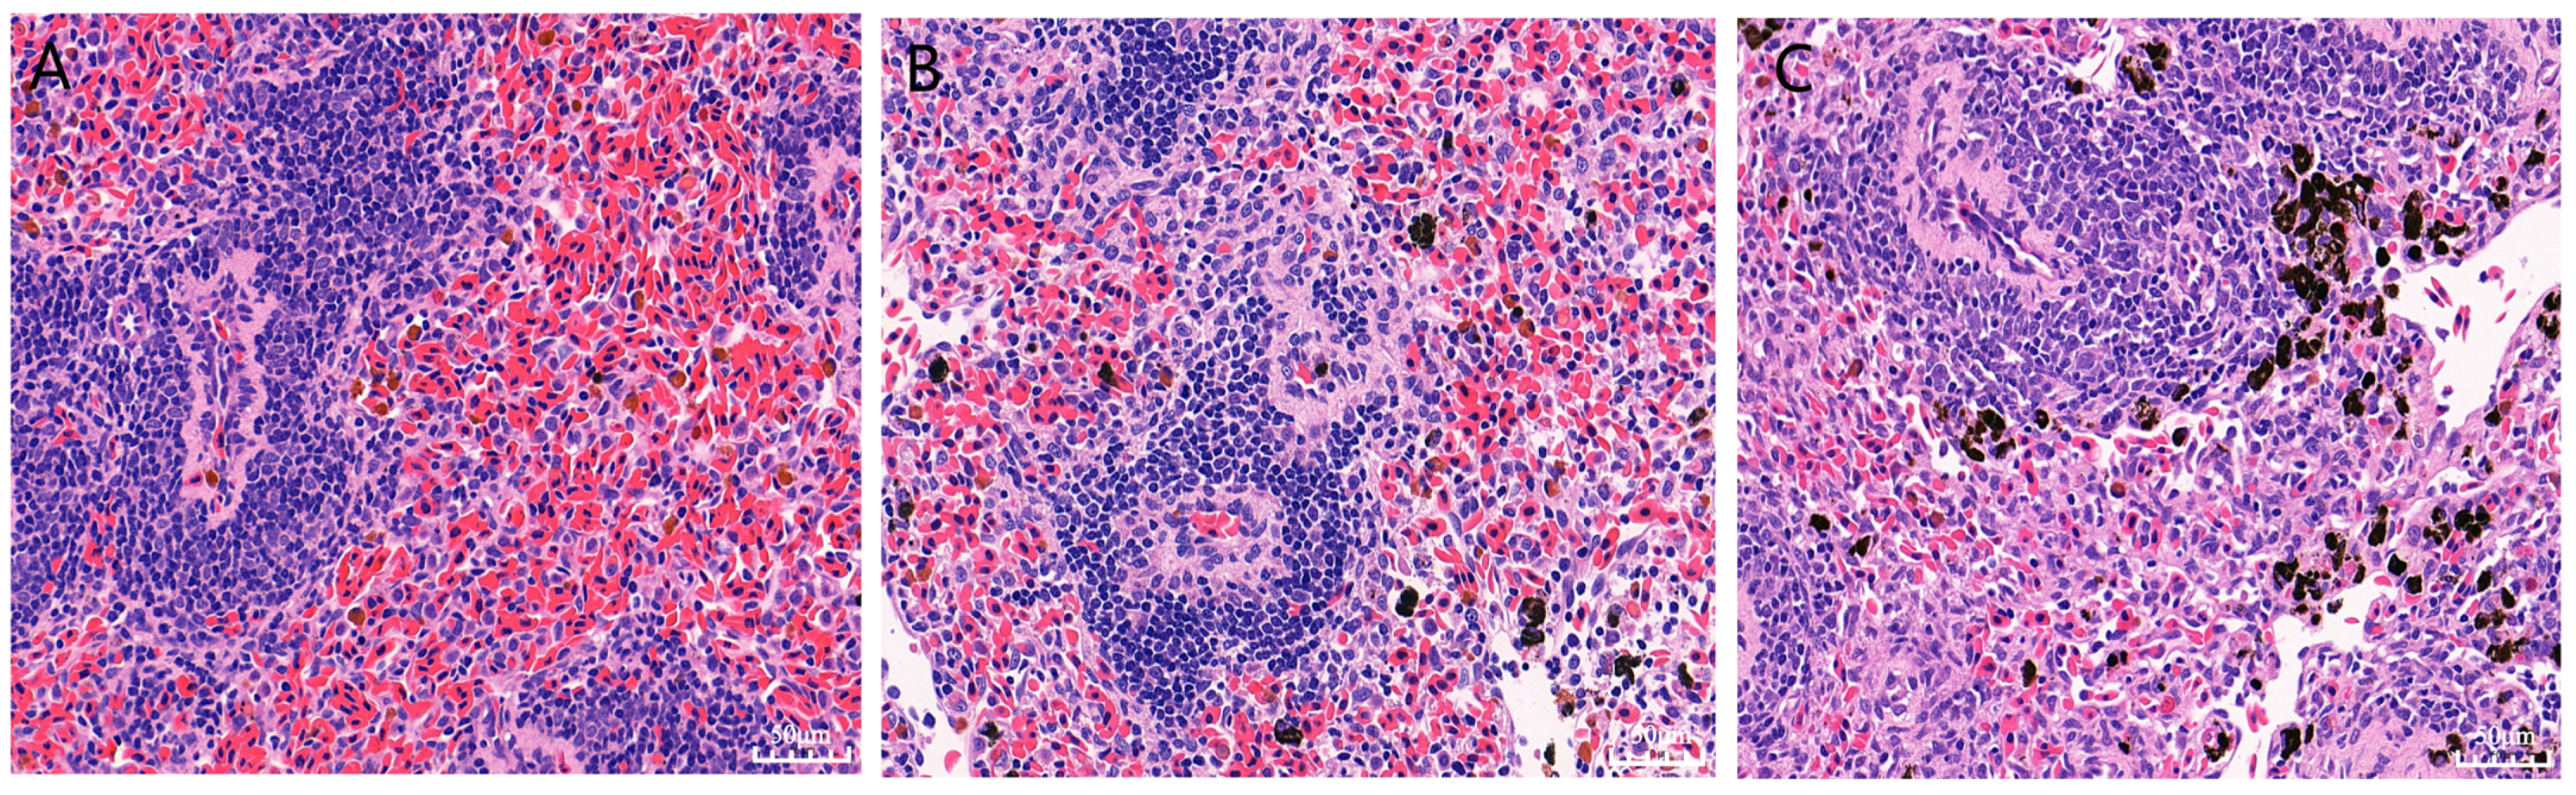

3.2. Pathological Analysis of the Chinese Soft-Shelled Turtles’ Spleens